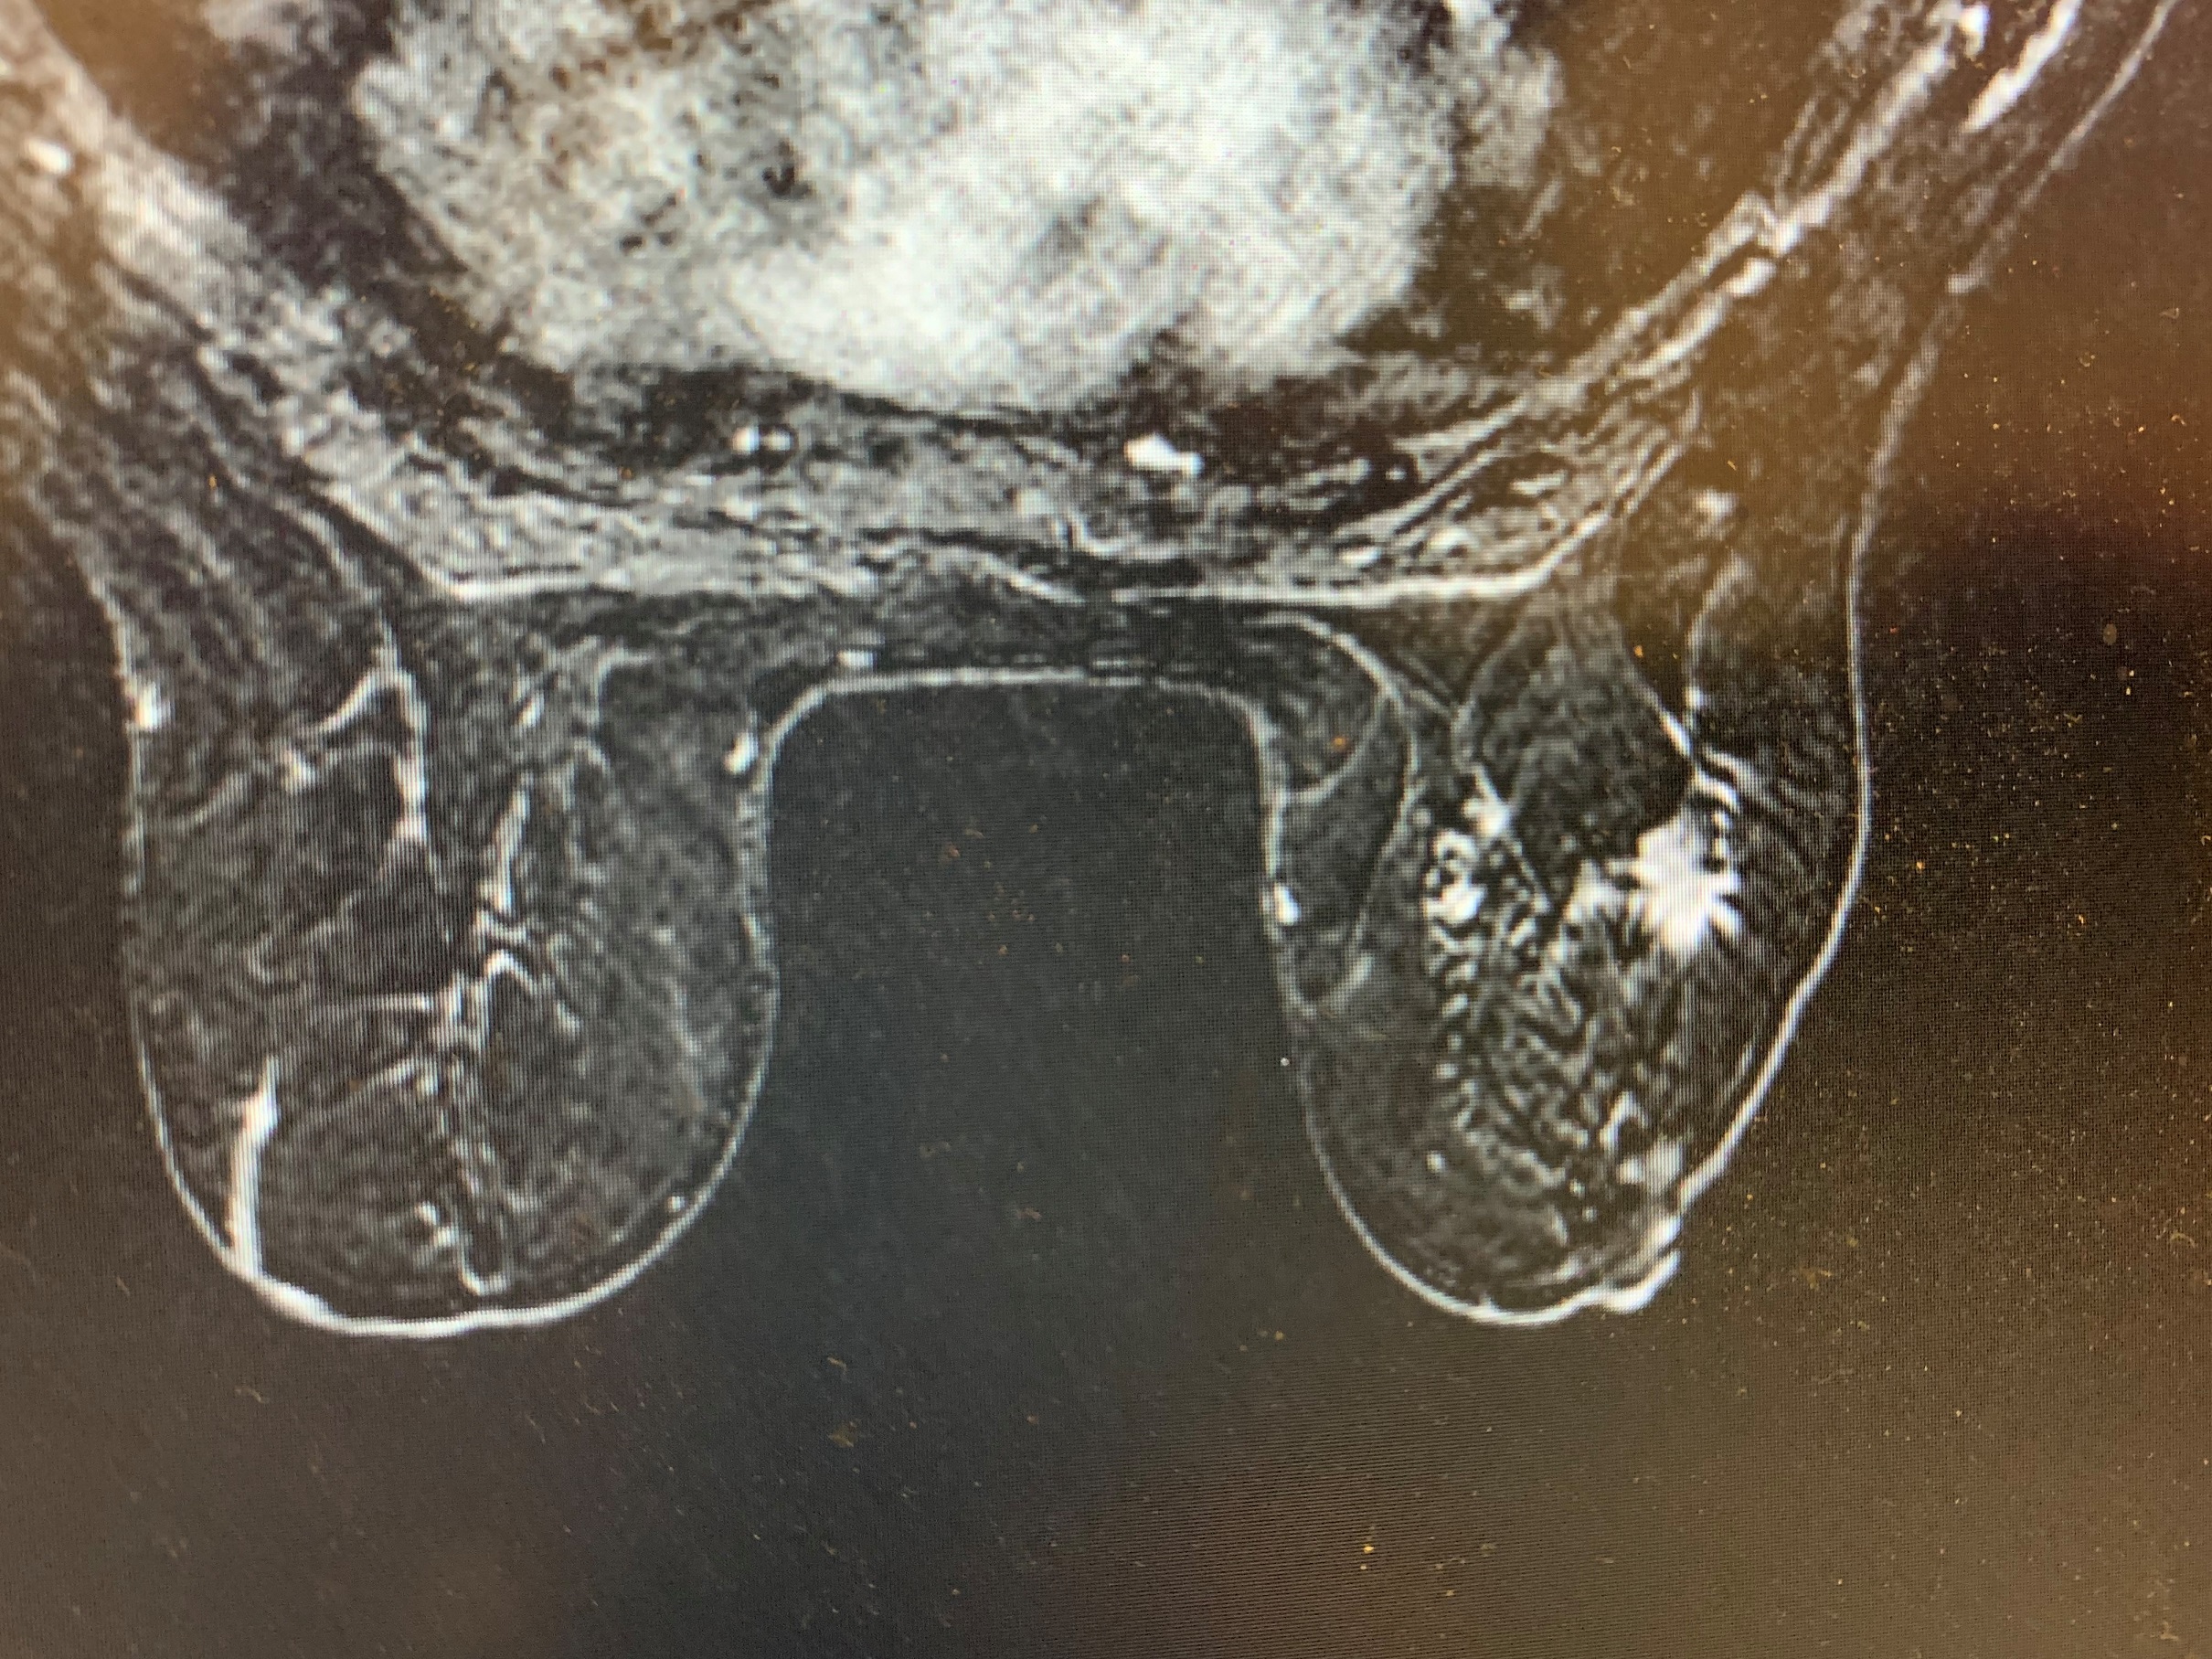

Pamje nga MRT-Mamografia